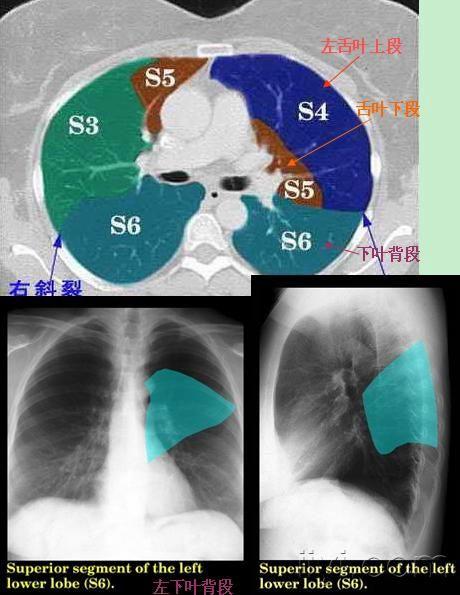

肺叶分段ct示意图,肺叶分段口诀

史上最全肺ct分段及典型疾病影像

肺的分段分叶解剖图ct

肺段ct划分解剖图

肺ct断层解剖示意图

肺的分段

肺叶分段ct

肺叶分段